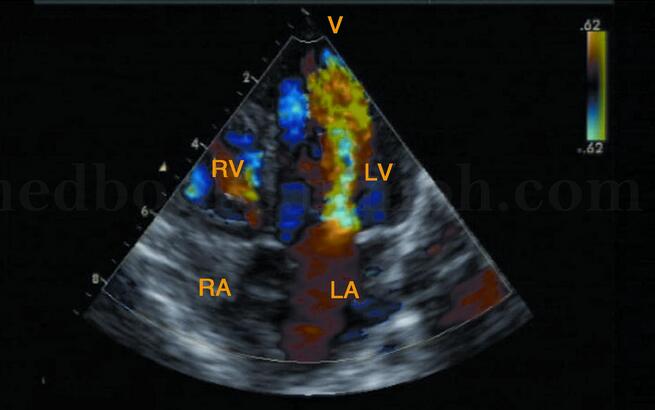

超声图片 如图2‐1‐120。

超声描述 经胸超声心动图检查:左心房扩大,右心房、右心室轻度扩大;二尖瓣前后叶增厚、回声强、交界处粘连,开放受限,前叶开放呈“气球样”改变,开放直径0.7cm,瓣口面积1.14cm2;肺动脉增宽36mm。M型超声见二尖瓣前后叶同向运动,呈“城墙样”改变。彩色多普勒血流显像(CDFI):舒张期二尖瓣口见多色镶嵌的射流束,正向流速2.4m/s,压差23mmHg,收缩期于右房内见源于三尖瓣口蓝色为主反流束,面积3.4cm2。

超声诊断 风湿性心脏病,二尖瓣中度狭窄,三尖瓣轻度反流(相对)。

图2‐1‐120 左室长轴切面见二尖瓣增厚、回声强、开放受限